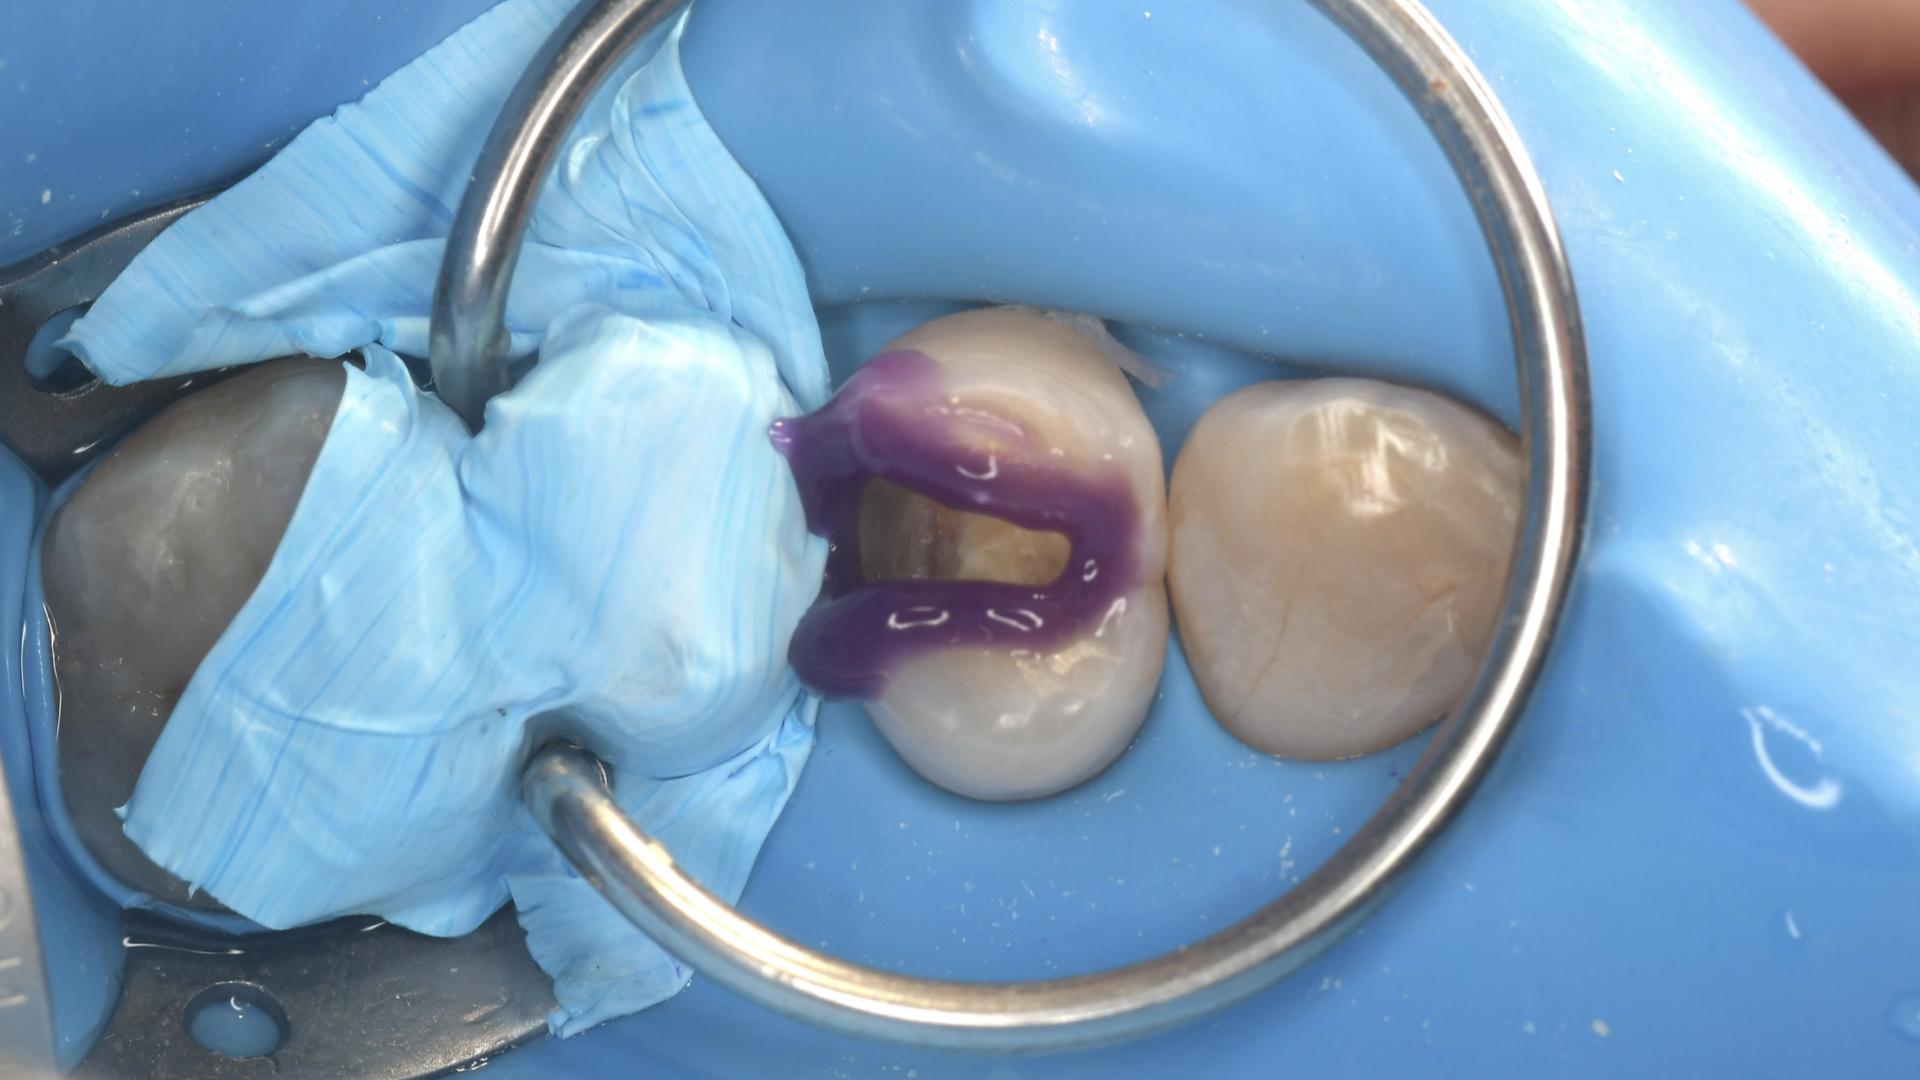

佐賀大和の小川歯科医院では、治療中に唾液や湿気が入り込まないよう、ラバーダム防湿を徹底。

さらに、**マイクロスコープ(歯科用顕微鏡)**を使用し、歯とレジンの境界を拡大しながら施術しています。

これにより、虫歯を完全に除去しつつ、接着面を最適な状態に保つことができ、

美しさと長期的な安定性を両立させています。